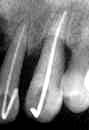

症例2

72歳・男性

術前4年4ヵ月

術直前(1986.6)

術直後

術後3年4ヵ月